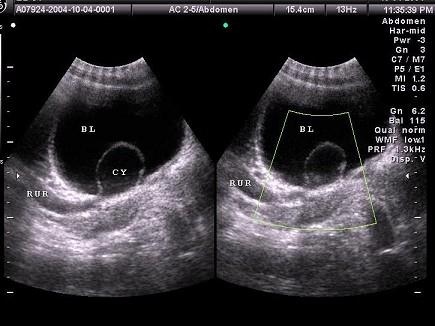

问题 女性,于膀胱输尿管位置见一囊性光团,有规律收缩,增大。如图所示,考虑为 ?(?)

选项 A.膀胱肿瘤 B.膀胱憩室 C.输尿管结石 D.输尿管囊肿 E.膀胱异物

答案 D